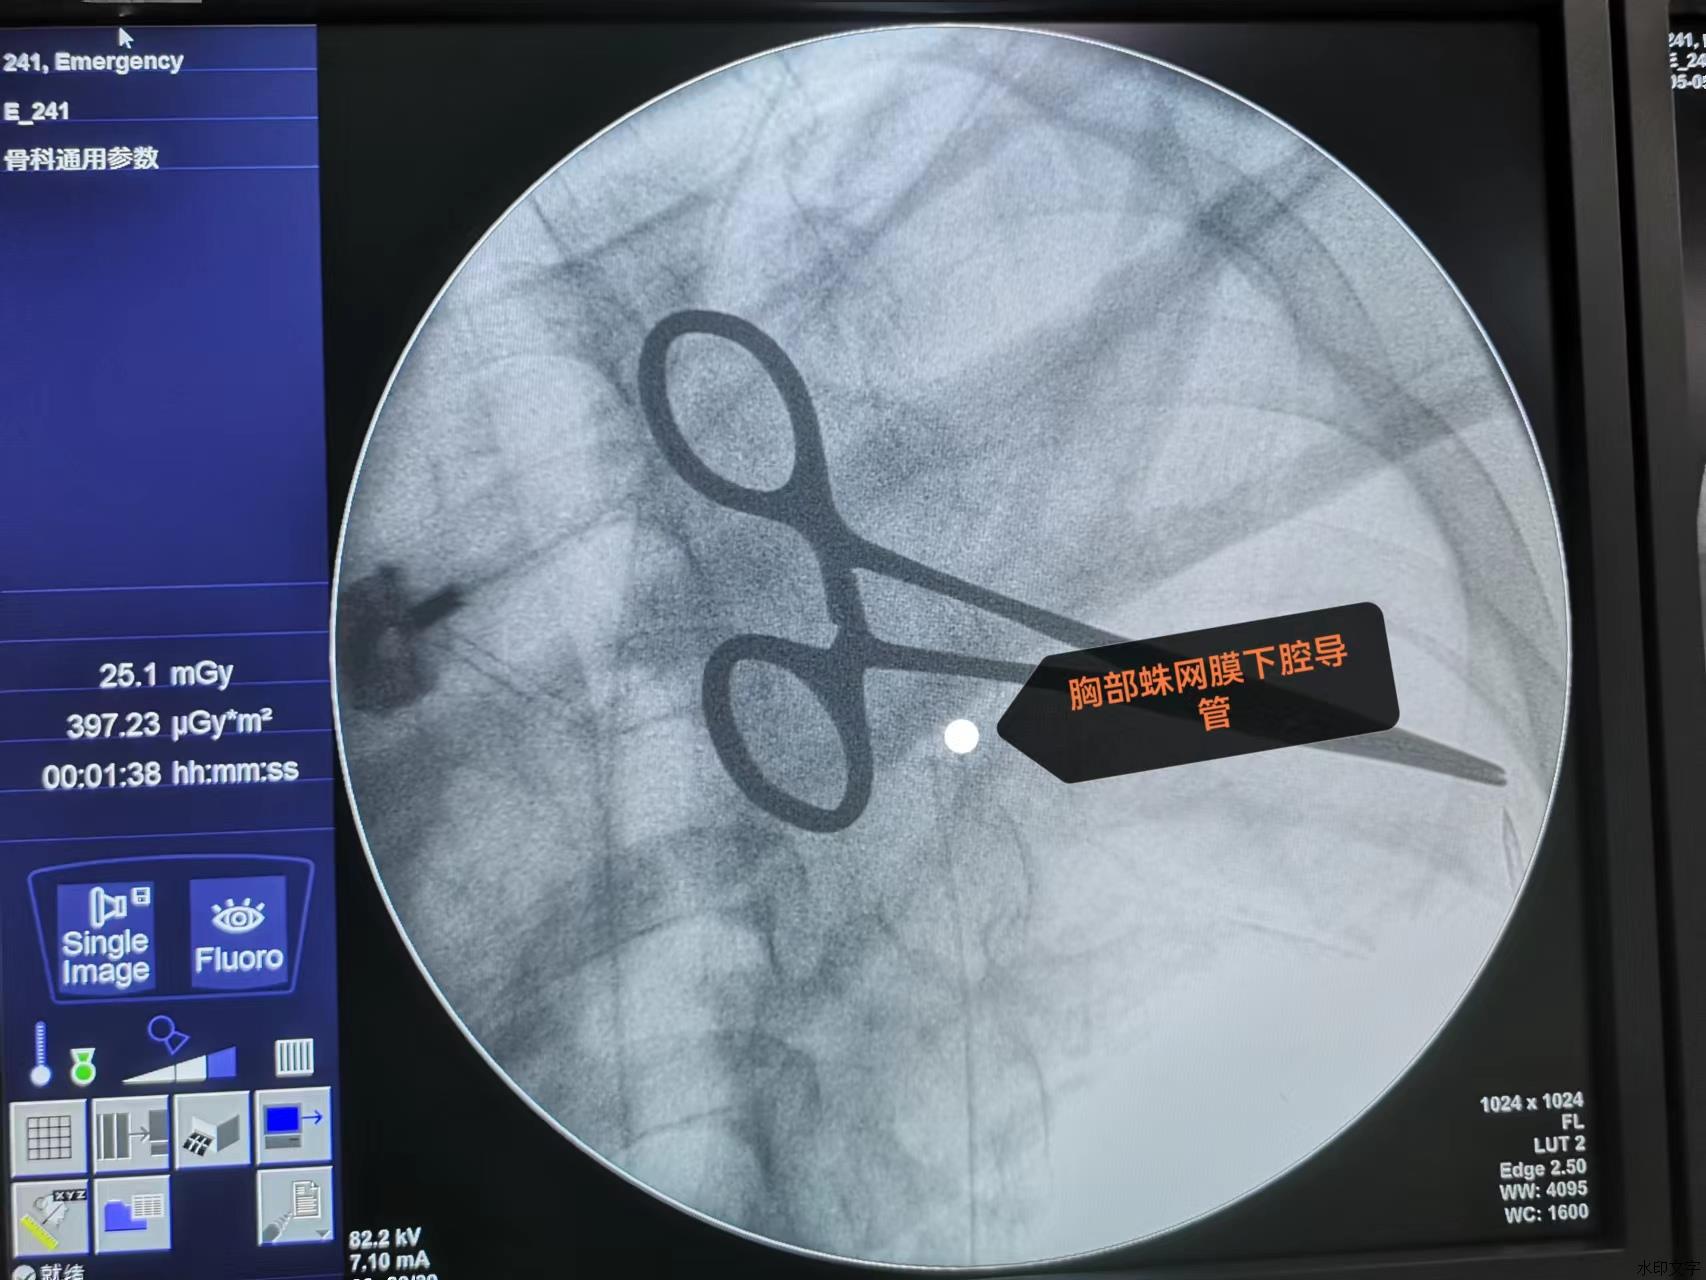

鞘内镇痛泵植入术是通过微创手术,将一个镇痛装置埋入皮下,外接镇痛泵持续或间断地输注微量止痛药物到蛛网膜下腔,阻断疼痛信号经脊髓向大脑传递达到镇痛作用。鞘内镇痛泵的用药量仅为口服药量的1/300,静脉给药量1/100,从而使药量大大降低,而且减少了药物不良反应。患者还可以根据自己疼痛程度自主调节用药剂量,体现了精准化医疗,舒适化医疗的理念。

为减轻患者疼痛,提高生活质量,经与患者及家属充分沟通,决定为其施行鞘内镇痛泵植入术。手术当天,镇痛效果良好,患者疼痛几乎消失。经过几天的心理治疗,该患者精神状态逐渐好转,进食明显增加,腹痛完全消失。患者感叹:“终于可以安安稳稳睡觉了!”